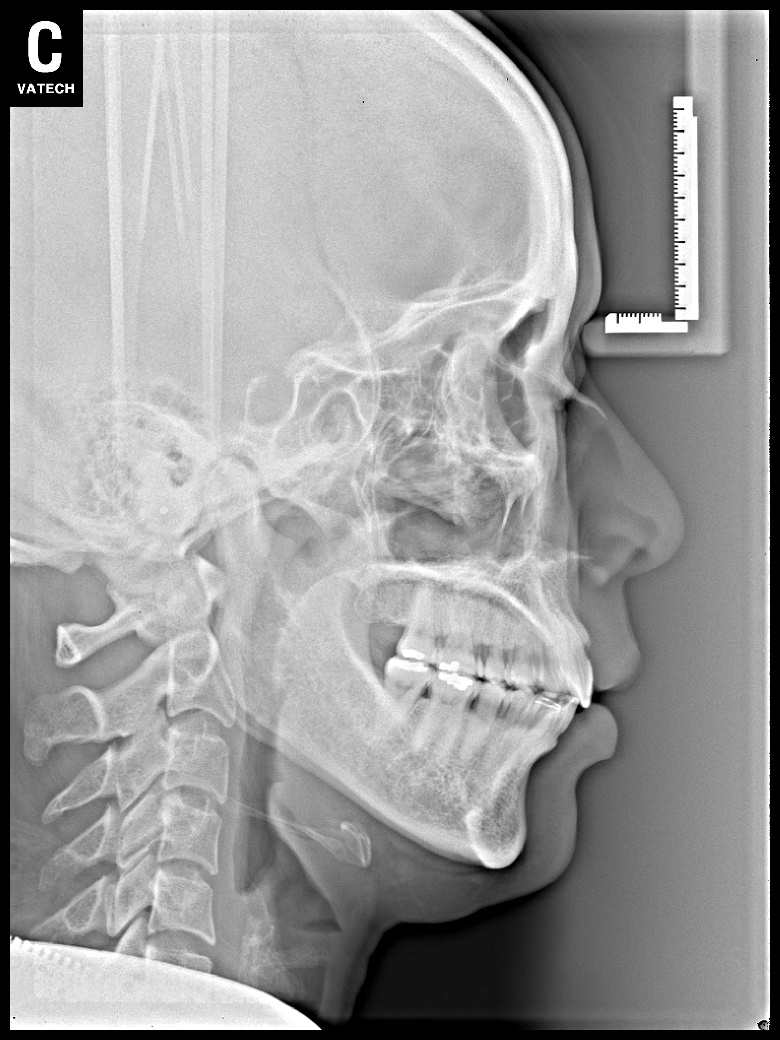

치료 전 사진입니다.